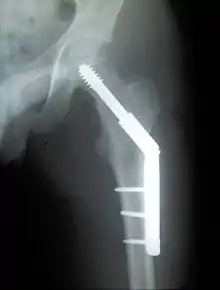

Closed reduction may not be satisfactory and open reduction then becomes necessary.[32] The use of open reduction has been reported as 8-13% among pertrochanteric fractures, and 52% among intertrochanteric fractures.[33] Both intertrochanteric and pertrochanteric fractures may be treated by a dynamic hip screw and plate, or an intramedullary rod.[32]

The fracture typically takes 3–6 months to heal. As it is only common in elderly, removal of the dynamic hip screw is usually not recommended to avoid unnecessary risk of second operation and the increased risk of re-fracture after implant removal. The most common cause for hip fractures in the elderly is osteoporosis; if this is the case, treatment of the osteoporosis can well reduce the risk of further fracture. Only young patients tend to consider having it removed; the implant may function as a stress riser, increasing the risk of a break if another accident occurs.